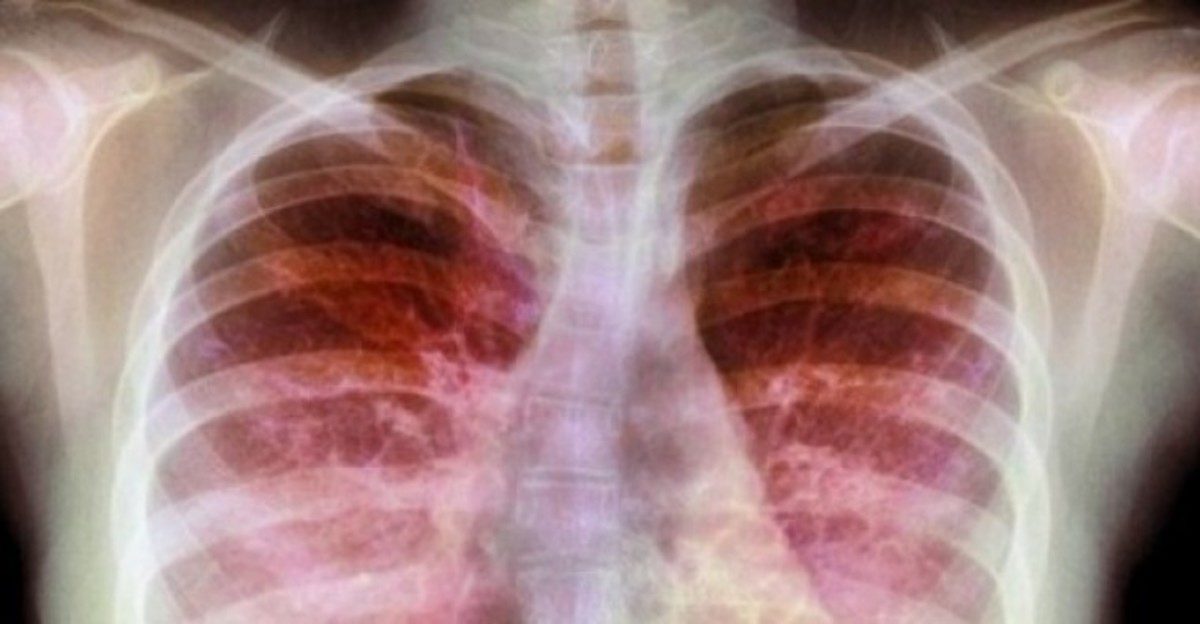

Με αφορμή την Παγκόσμια Ημέρα Κυστικής Ίνωσης (8 Σεπτεμβρίου), το ΙΑΣΩ Παίδων προσφέρει την εξέταση Test Ιδρώτα στην προνομιακή τιμή των 70 ευρώ για όλο το μήνα Σεπτέμβριο. Η εξέταση διαρκεί μισή ώρα και το αποτέλεσμα της δίνεται την ίδια ημέρα. Κατά τη διάρκεια της δοκιμασίας, πραγματοποιείται ταυτόχρονα παιδοπνευμονολογική συμβουλευτική για τα αναπνευστικά προβλήματα του παιδιού.

Το τεστ ιδρώτα αποτελεί την πλέον αναγνωρισμένη μέθοδο διεθνώς για την ανίχνευση μικρών ασθενών που πάσχουν από κυστική ίνωση. Το ΙΑΣΩ Παίδων, θέλοντας να παρέχει ό,τι καλύτερο στη φροντίδα των παιδιών, αναβαθμίζει τις υπηρεσίες του και επενδύει σε ιατρικό εξοπλισμό τεχνολογίας αιχμής.

Το 4-5% του γενικού πληθυσμού, δηλαδή 1 στα 20 έως 25 άτομα θεωρείται ότι είναι φορέας του παθολογικού γονιδίου (περίπου 500.000 Έλληνες είναι φορείς). Ως εκ τούτου, υπάρχει αυξημένη πιθανότητα να γεννηθεί παιδί με κυστική ίνωση. Τα συμπτώματα που παρουσιάζει συνήθως κάποιος που νοσεί είναι κυρίως χρόνιος βήχας, βρογχίτιδες ή υποτροπιάζουσες βρογχίτιδες, ανεπαρκής πρόληψη βάρους.